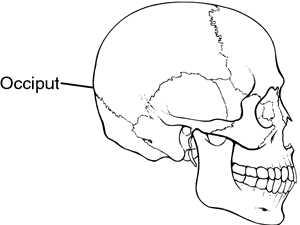

occiput or occipital region

- the hard region of the vertebrate cranium.

https://medical-dictionary.thefreedictionary.com/occipital+region

Original anzeigen (0,3 MB)Das Hinterhauptbein (auch Hinterhauptsbein; lat. Os occipitale [1] oder kurz Occiput) ist der am Halsübergang gelegene Teil des Hirnschädels. Es bildet den hinteren Abschluss der Schädelhöhle und mit dem Atlas das erste Kopfgelenk.

7. Hinterhauptbein (Os occipitale) (grün)Wikipedia: Hinterhauptbein